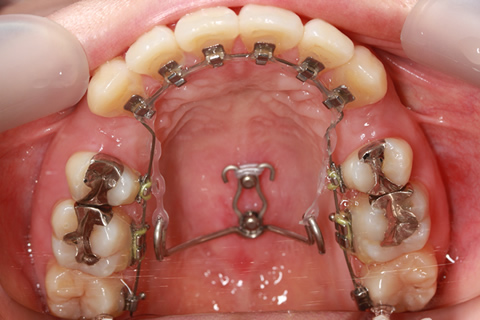

最新鋭の口蓋骨アンカースクリューを導入!

スピーディで確実な治療結果に期待!最新鋭の口蓋骨アンカースクリューを矯正治療に導入しました。まず痛そうですが、痛みはほとんどありませんのでご安心下さい。歯列不正を引き起こしている原因は本当に様々な要素が相まっています。歯の位置、歯の大きさ、顎の幅、上下のアゴの位置関係、etc...矯正治療開始される患者様の2割はかなりシビアな状態であり、今までの矯正治療では100%の状態までキレイに治せないものでした。

初期のアンカースクリューは固定源として使うだけのものでしたが、矯正歯科界を代表する重鎮の先生方により進化していき、上顎の口蓋正中部に埋入したスクリューに、専用ワイヤーを装着することで、大臼歯のコントロール、前歯部のリトラクション、他多くのメカニクスのアンカレッジとして使用できるようになりました。

これにより、どんな歯並びも怖くありません!当院のアンカースクリューを駆使した矯正治療にお任せ下さい。(注)スクリューを入れた方が良さそうな場合のみ、カウンセリング時にご説明いたします。痛そうだし、怖いから入れたくない方は遠慮なくおっしゃってください。他の方法を検討します。